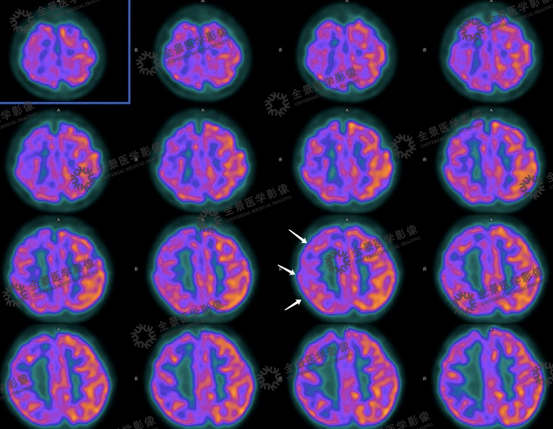

病史:患者女性,14岁,7岁起癫痫,目前口服药物治疗,2019年11月起发作频繁。2020年03月24日来我中心行头颅PET/CT断层显像。左侧顶叶局部脑皮质下沟回样密度减低伴相邻皮层FDG代谢较对侧减低。(孙毅)

左侧顶叶局部脑皮质下沟回样密度减低伴相邻皮层FDG代谢较对侧减低。